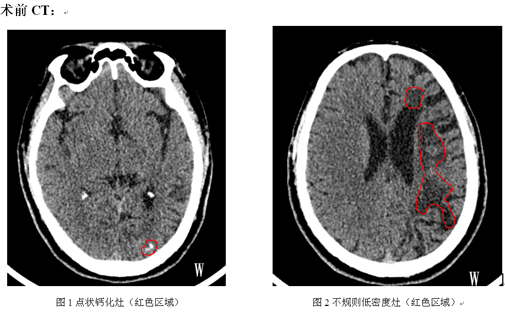

入院查体:神经系统检查未及明显阳性体征。头部CT示:左枕局部可见钙化影(如图1),左侧额顶枕多发软化灶(CT表现为低密度灶,如图2)。头颅MRI增强扫描后显示:1.左侧额顶枕叶及左侧基底节区多发病变,现增强后左侧枕叶病变异常强化,考虑存在寄生虫感染(脑裂头蚴病可能)2.脑白质少许脱髓鞘灶;3.脑干偏左侧缩小,考虑沃勒变性。血/脑脊液化验示寄生虫抗体IgG/IgM:阳性。

1.CT扫描:1922年Chang KH等认为该病在CT检查有以下三联征表现:1.白质区不规则的低密度占位灶,伴有临近脑室略微扩张,反映白质退行性病变;2.点状钙化灶;3.病灶结节状或不规则增强,提示活动的感染肉芽肿。